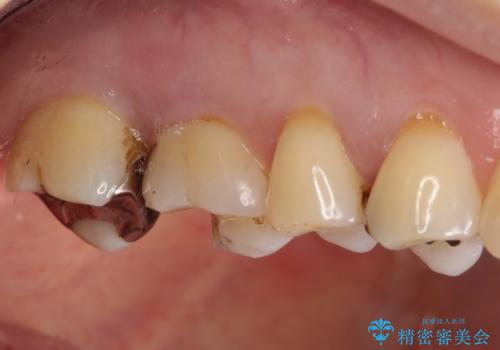

- 銀歯が外れて、中が虫歯になっているところがありました。

虫歯を取り除き、ゴールドインレーを装着する治療計画としました。